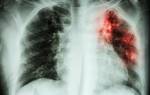

Легочное кровотечение или легочное кровохарканье — это уже симптом туберкулеза на поздней стадии; заметив его, нужно срочно обратиться к врачу для диагностики, поскольку кровохарканье — симптом и других серьезных заболеваний, и неотложного купирования кровохарканья и лечения «.

image